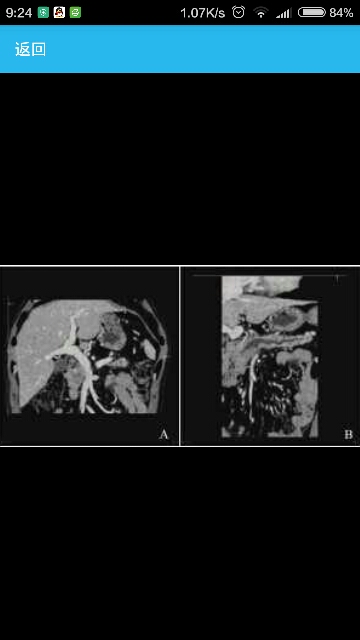

患者,男,42岁  病史6年前行右臀部纤维瘤切除术。1月前无明显诱因出现上腹部持续性隐痛,可耐受,伴恶心,无呕吐,于当地医院查腹部B超显示:胰头区低回声团块,大小约2.6cm×2cm,内部回声不均匀,边界尚清晰,形态欠规则,主胰管扩张,最宽处1cm。血淀粉酶(AMY)升高达160U/L,尿AMY升高达815U/L。肿瘤标记物癌胚抗原CEA、糖链抗原19-9均正常,结合CT平扫+增强考虑恶性病变,遂于2012年12月6日来北京协和医院就诊。 辅助检查入院查肿瘤标记物:糖链抗原242(CA242)、甲胎蛋白(AFP)、CEA、CA19-9均正常。腹部CT增强+胰腺三维重建结果显示:胰头区软组织密度占位,大小约2.3cm×2.9cm,边界欠清晰,平扫CT值约63HU。增强后:动脉期CT值约63HU,门脉期CT值约87HU,延迟期CT值约79HU,增强后各期均低于周围正常胰腺组织(图1)。 中远段胰管扩张,病变与部分肠系膜上静脉分界不清,肠系膜上静脉与门静脉汇合处略受压变窄(图2),肝门区及胰周可见多发淋巴结。PET-CT显示胰头区病灶代谢轻度增高。Whipple术后病理结果显示:胰腺内可见梭形肿瘤细胞浸润,局灶侵达胰腺周围脂肪组织,未及胆总管及十二指肠。小肠、胰腺及胆总管断端未见肿瘤细胞,胆囊未见特殊,淋巴结可见肿瘤累及(胰周1/6,小肠周0/1)。免疫组织化学结果显示:Vimention(+),CD34(血管+),CD68(散在+),AE1/AE3、Bcl-2、CD21、CD35、CgA、S-100、SMA、Syn、CD117和HMB45均阴性,Ki-67指数约15%。 病理结合免疫组织化学结果确诊为硬化性纤维肉瘤。